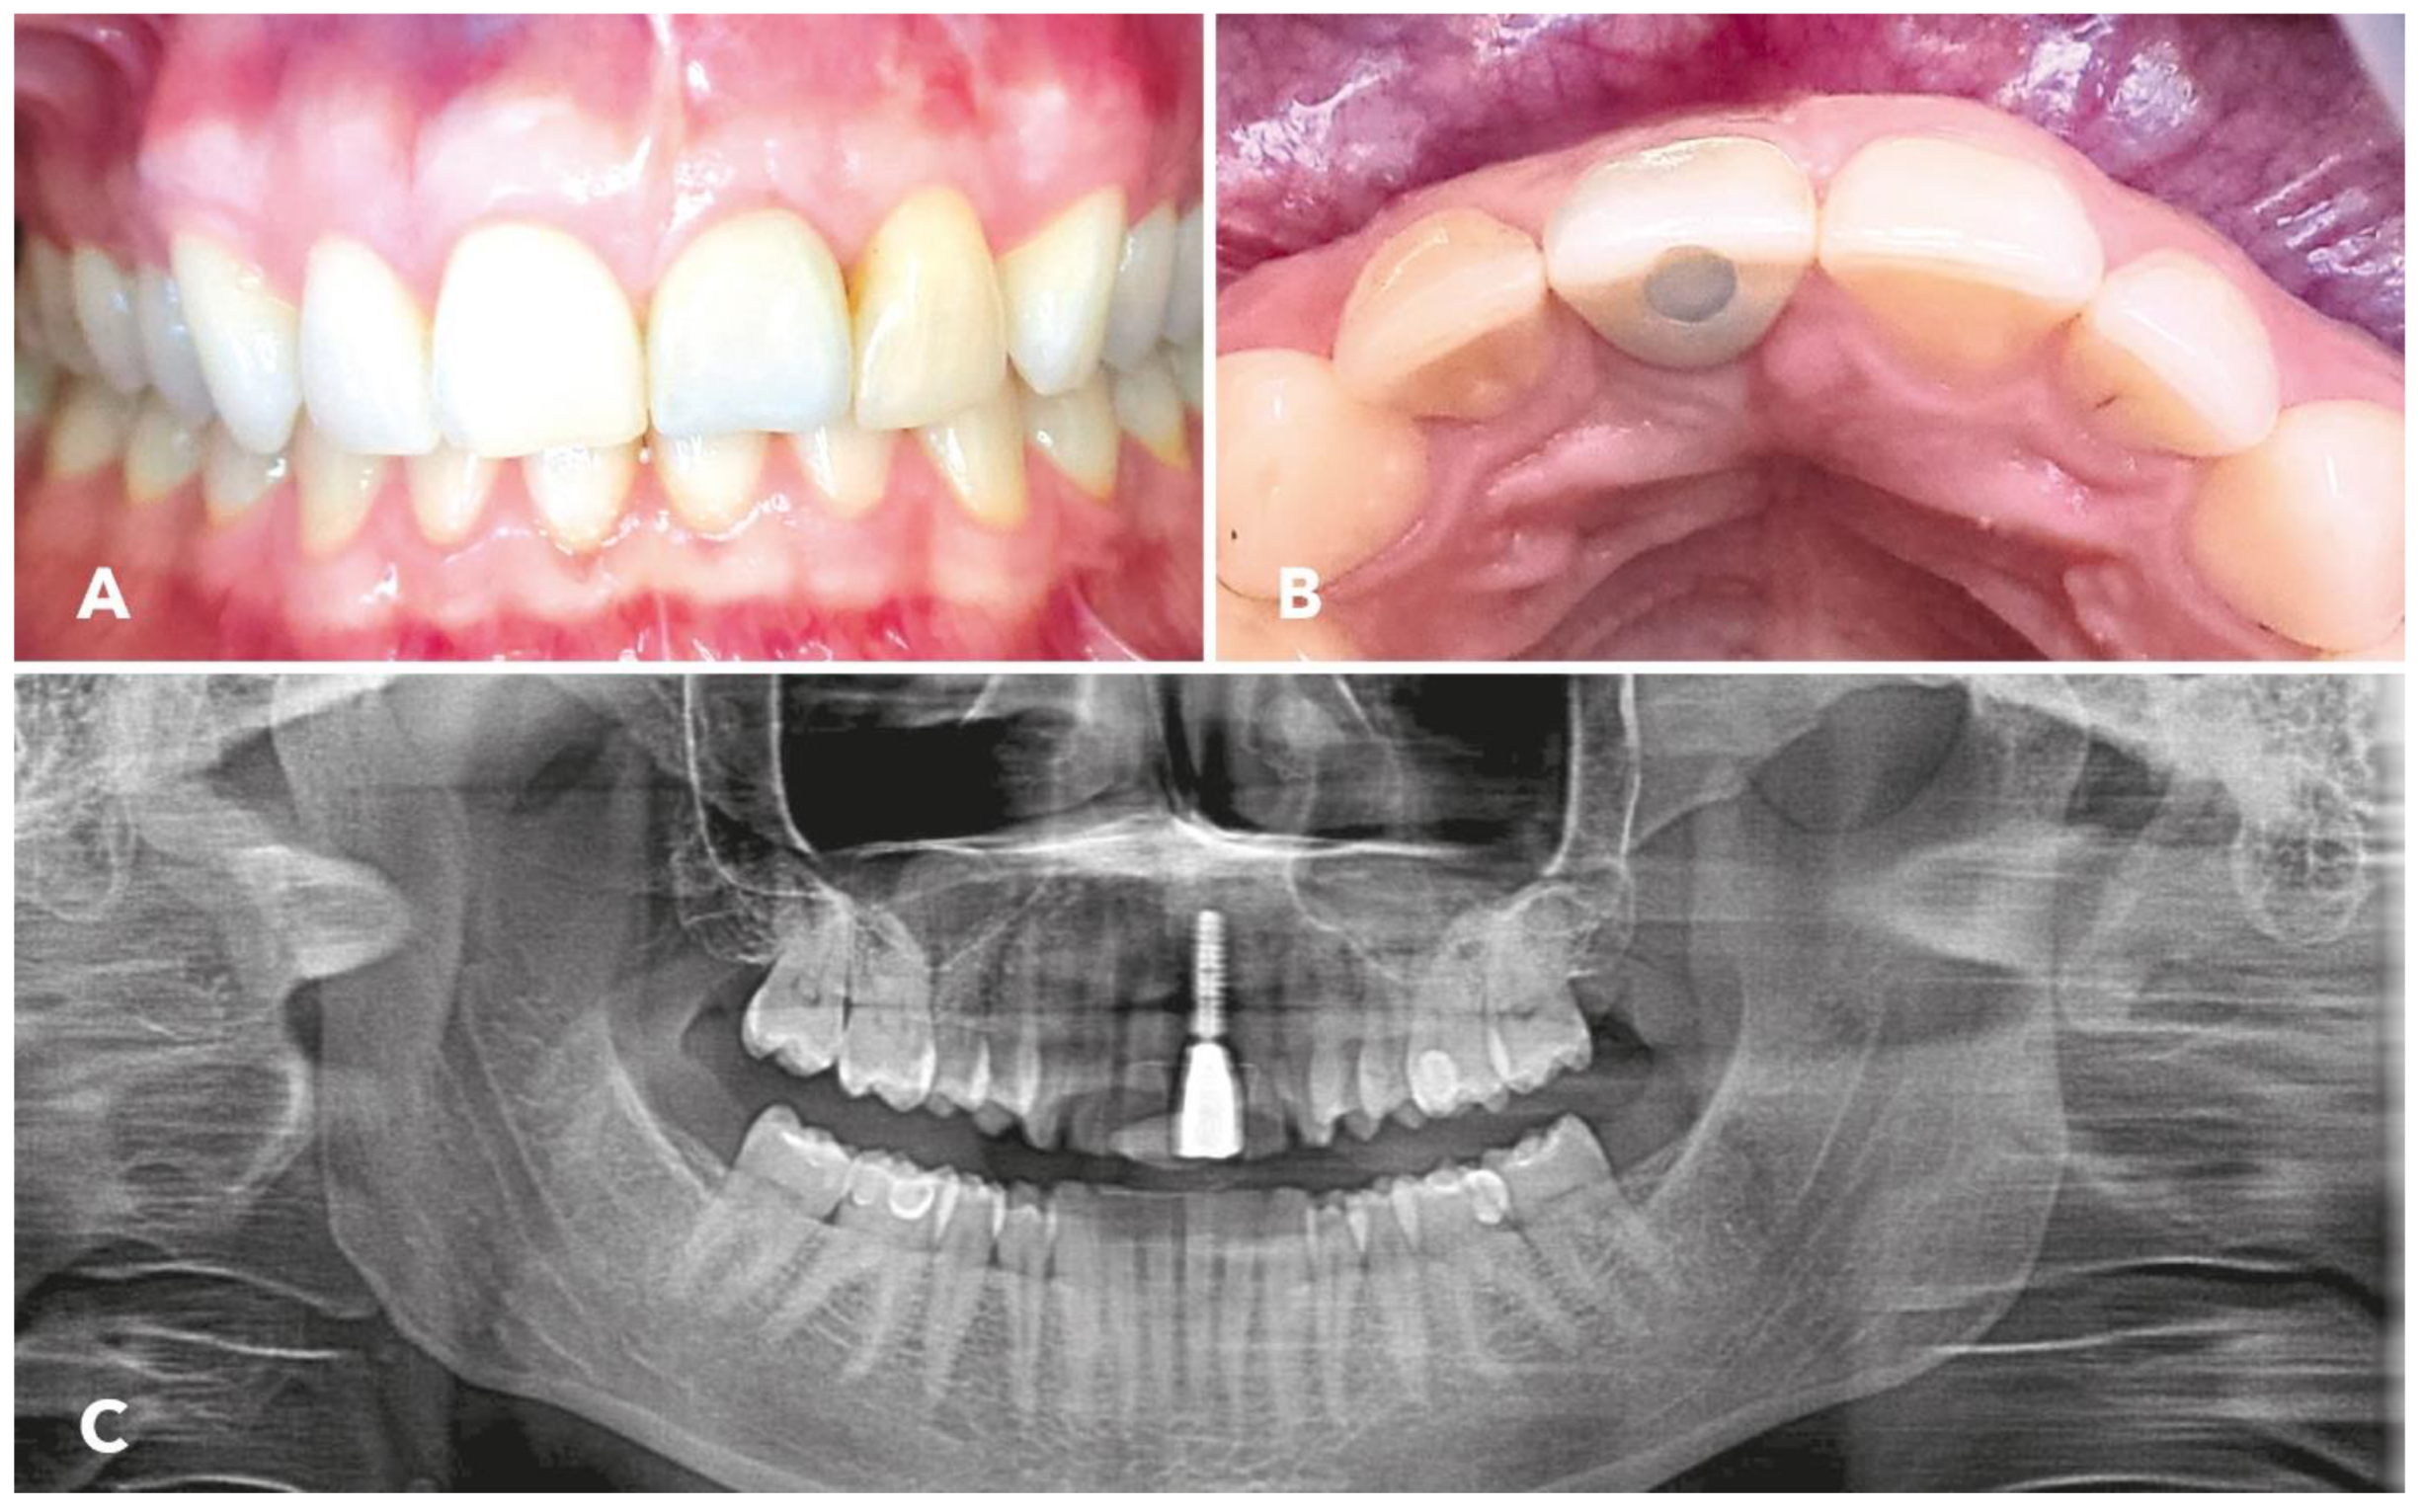

3. Results

2.5. Implantation